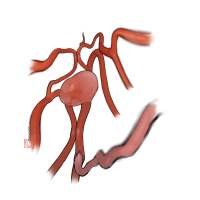

術後イラストシリーズ